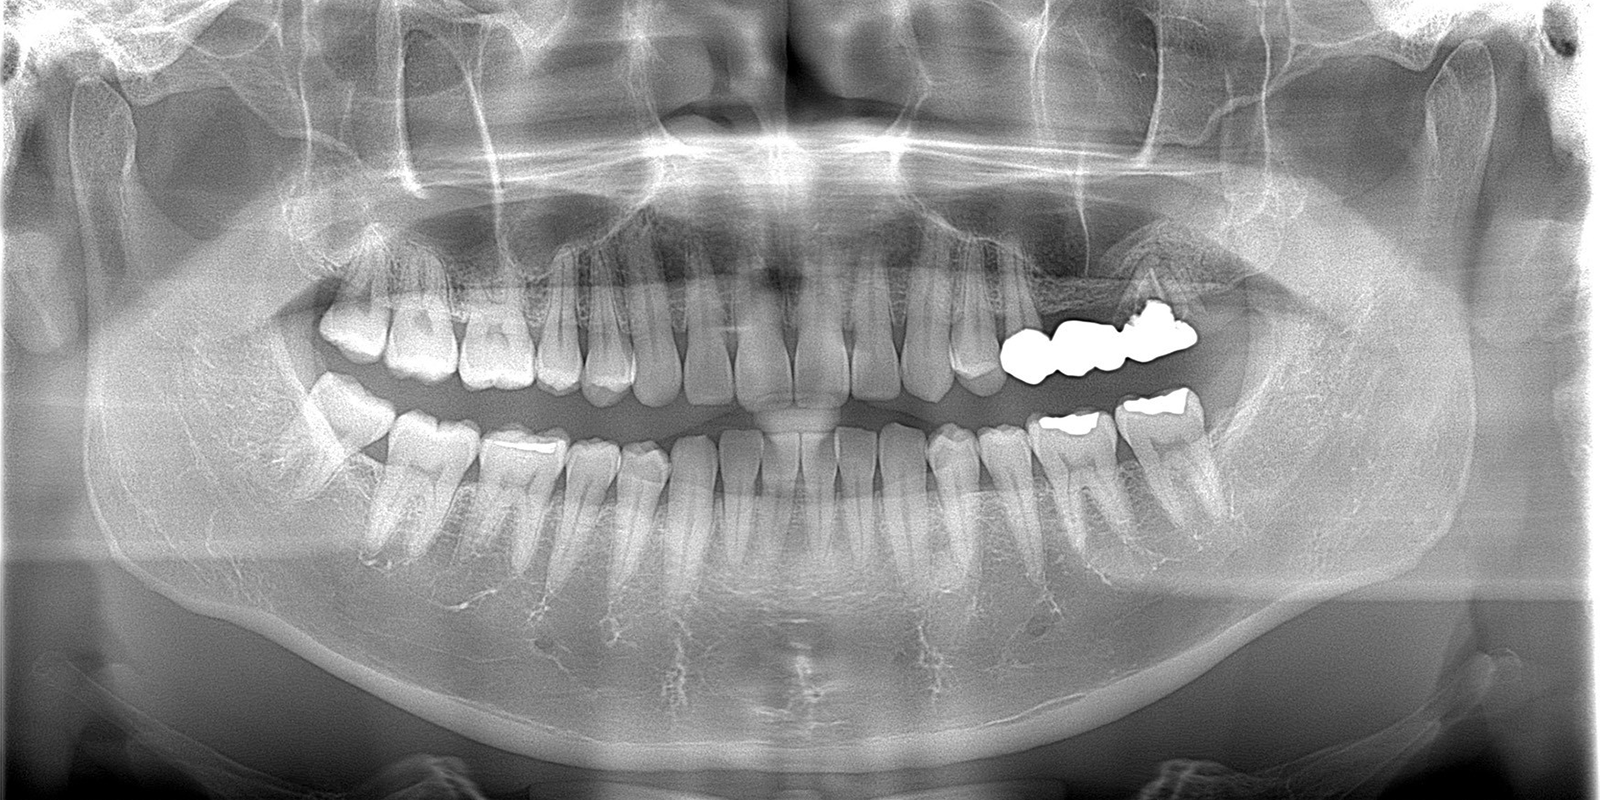

この患者様は、左上を噛むと痛いとのことでご来院されました。

他院でセットしたブリッジを除去してみると、歯根(歯の根っこ)部分が破折しており、抜歯となりました。患者様のご希望により、抜歯後はインプラント治療を行うこととなりました。

レントゲン画像をよく診てみると、歯が破折した部分から、歯槽骨内に感染が拡大しており歯槽骨がかなり吸収してしまっている事が分かります。また、抜歯後はさらに骨高径(骨量)が減ってしまいます。抜歯後のCT画像を見てみると、一番骨が薄いところで3.35mmしかないことが分かります。